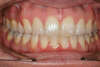

Décalage traité par gouttières

Fin de traitement